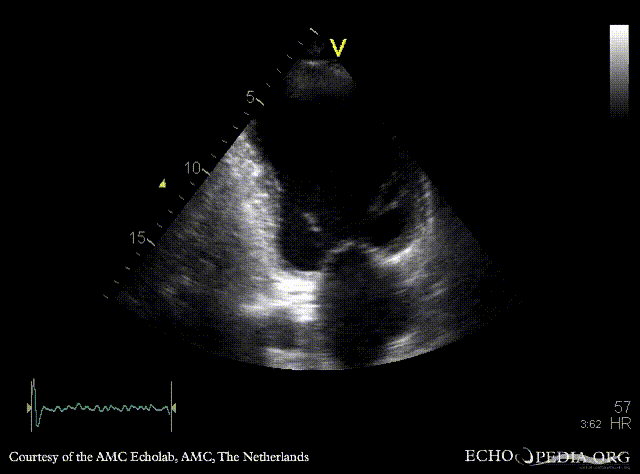

| Courtesy of: AMC Echolab, AMC, The Netherlands | |

| A4CH: apical aneurysm of left ventricle | A2CH: apical aneyrysm of left ventricle |